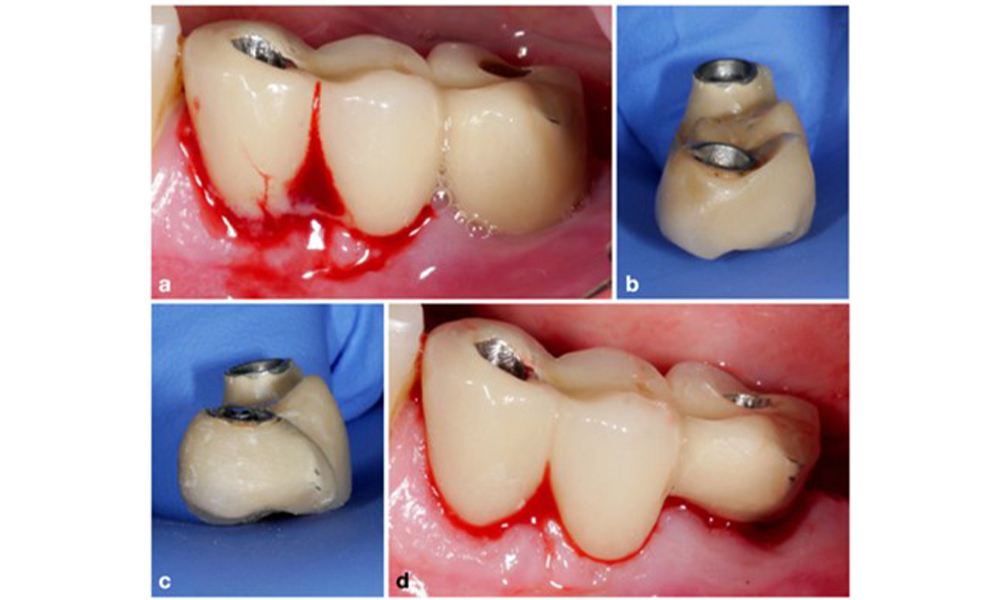

The World Workshop on the Classification of Periodontal and Peri‐Implant Diseases and Conditions from 2017 established diagnostic criteria for peri-implant mucositis and peri-implantitis (Renvert et al. 2018). Peri-implant mucositis is defined as (1) presence of inflammation around the implant (i.e., redness, swelling, line or drop of bleeding within 30 seconds of probing), combined with (2) no additional bone loss after initial healing (figure 1).

Implant in position 26 with peri-implant mucositis (a–c). The probing depth value of 5 mm (b) remains consistent with the measurement taken a few weeks after placing the prosthetic reconstruction. There is bleeding on probing (c) but the radiograph indicates no additional bone loss beyond what is expected for marginal bone remodelling (d).

Figure 1. Implant in position 26 with peri-implant mucositis (a–c). The probing depth value of 5 mm (b) remains consistent with the measurement taken a few weeks after placing the prosthetic reconstruction. There is bleeding on probing (c) but the radiograph indicates no additional bone loss beyond what is expected for marginal bone remodelling (d).